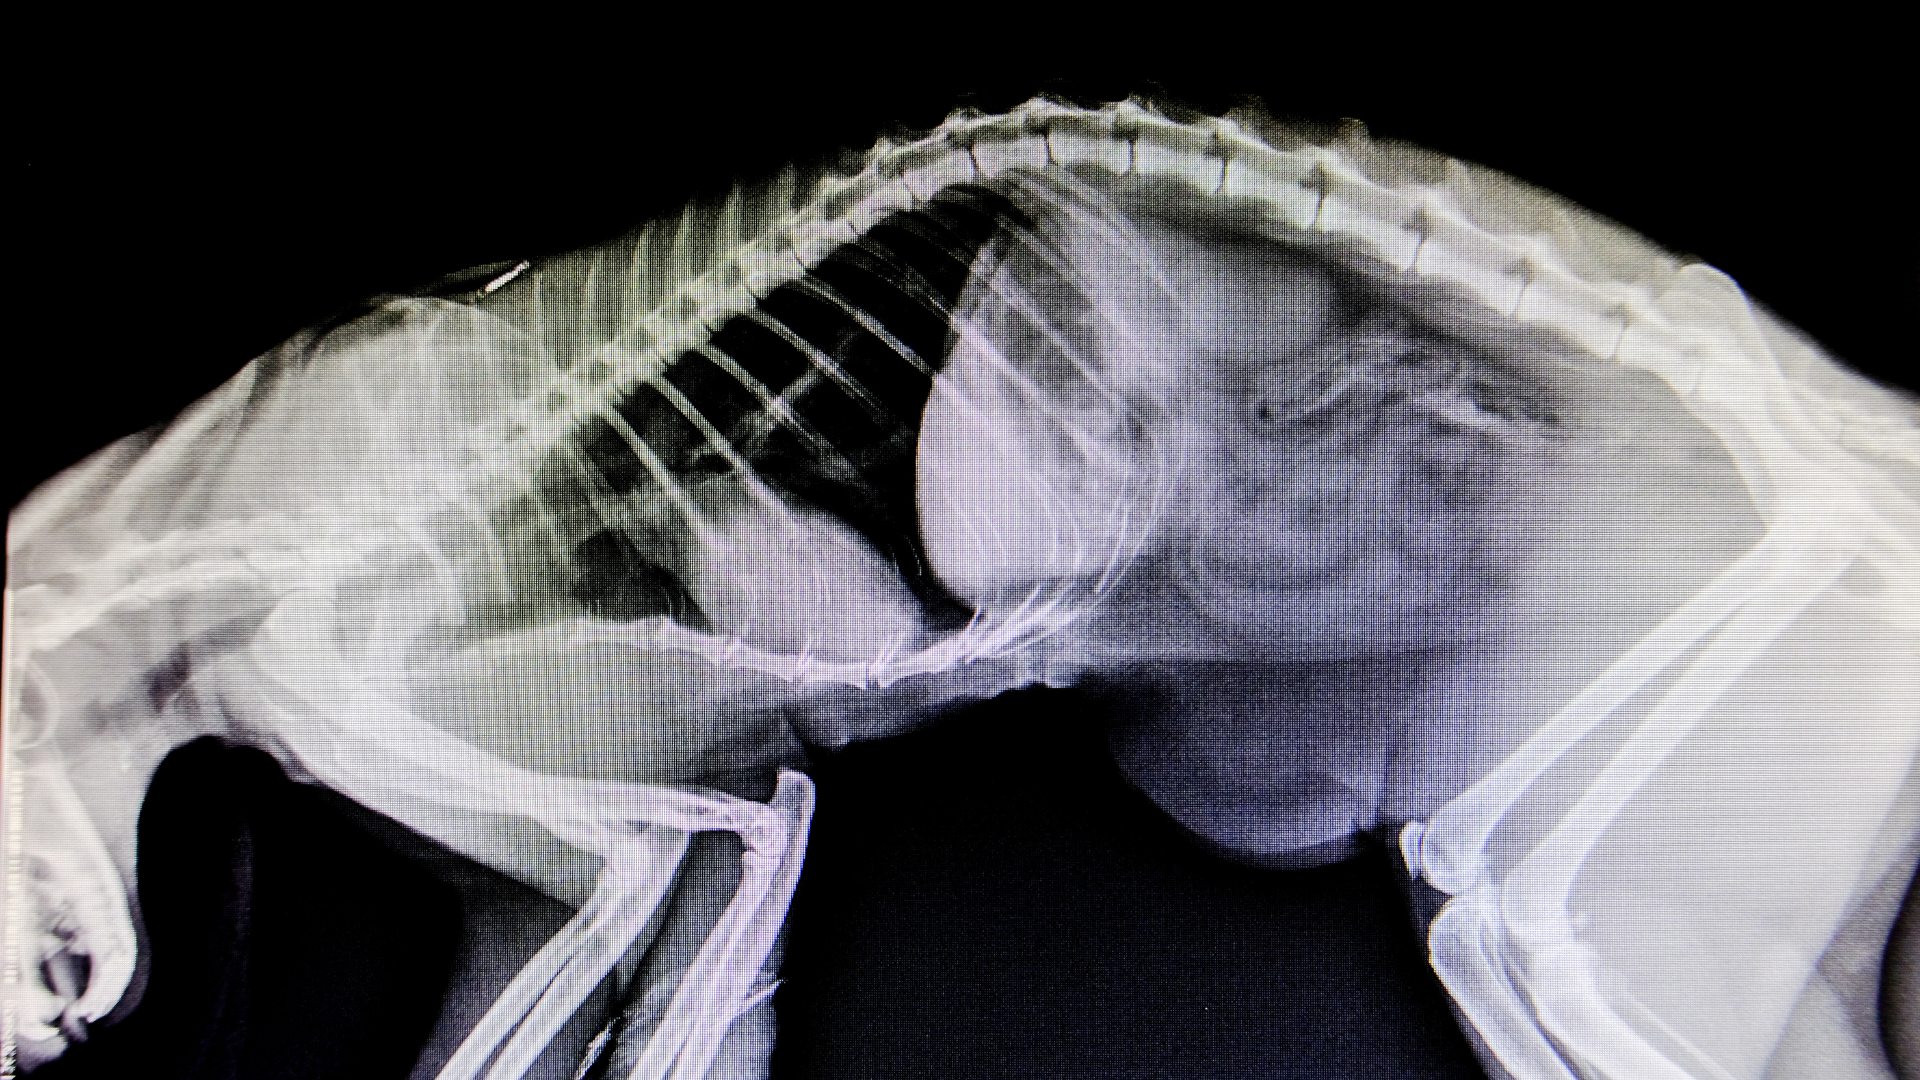

Our state-of-the-art radiology equipment produces clear, detailed images of your pet’s internal structures — including bones, joints, chest, and abdomen. These digital radiographs can detect fractures, foreign objects, tumors, heart or lung disease, and other abnormalities that might not be visible during a physical exam. Because the images are digital, results are available within minutes, enabling our team to begin diagnosis and treatment without delay.